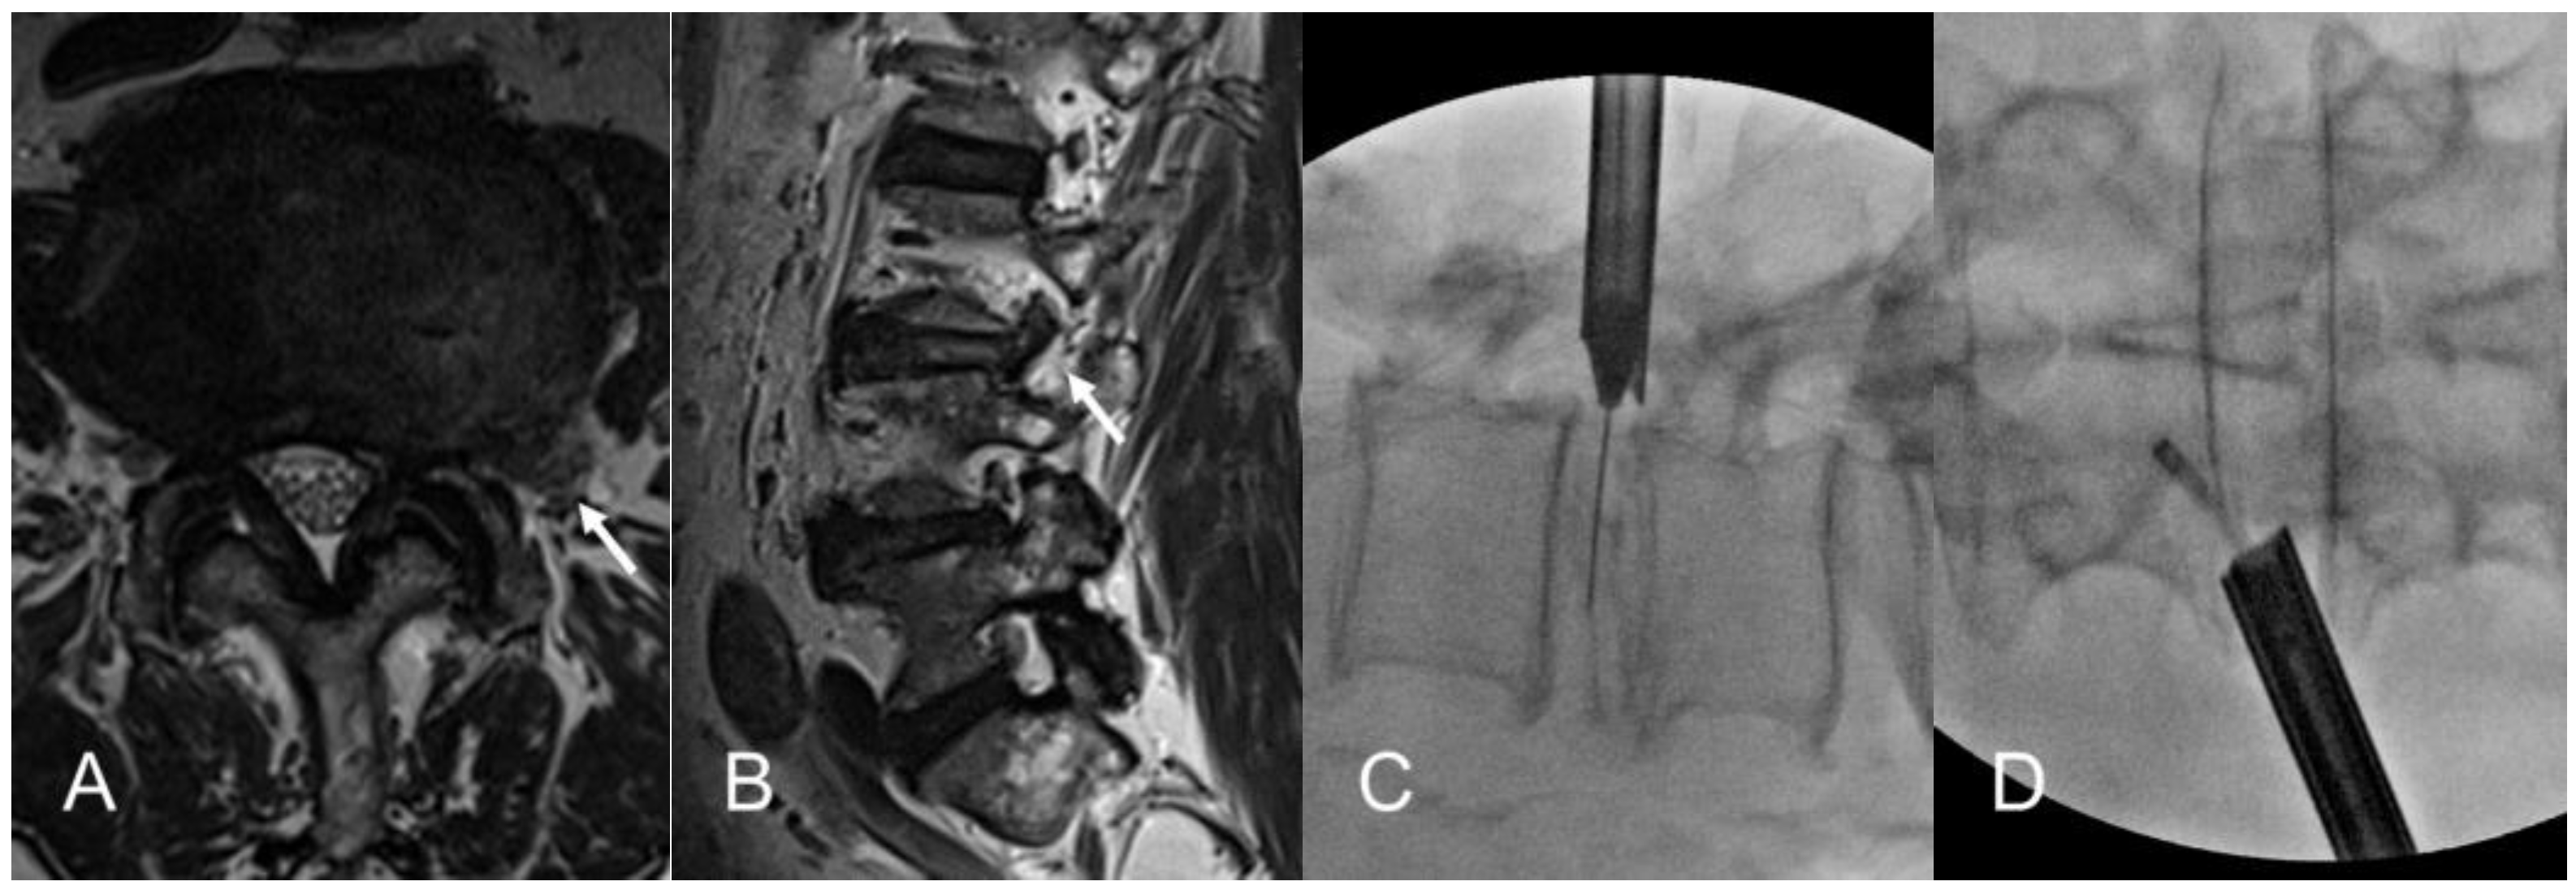

2.2.2. Transforaminal Approach Under Fluoroscopic Guidance

2.2.3. Selective Discectomy Under Endoscopic Visualization